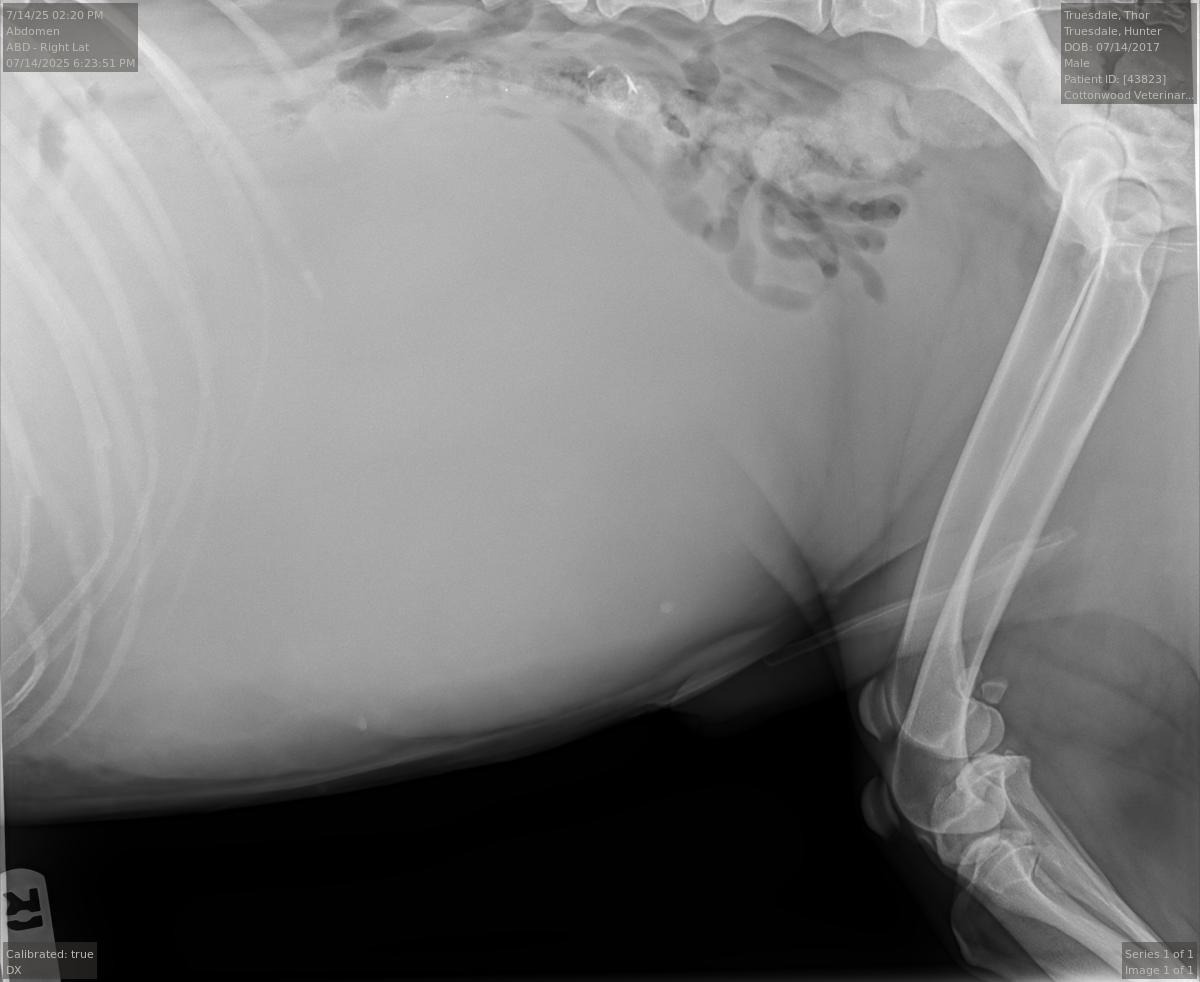

My name is Hunter and anyone that knows me knows my dog is Thor boy. I have had him since he was 9 weeks old and he is currently 8, going on 9. It saddens me deeply to make this post, but I may have as little as 2 weeks left with this amazing companion. He has been by my side through it all, and I couldn't have made it through all the dark times without him ❤️. He was recently seen by a vet for signs of bloating. He was still acting normal, eating, and drinking just like any other day. I just noticed he was losing weight for no apparent reason. He also appeared to have lost muscle mass, yet his vet said he had gained roughly 7 lbs. X-rays revealed a giant mass or fluid build-up in his abdomen. The X-ray provided should show all of his organs; however, you will notice they show none. The ultrasound revealed a mass the specialist says he's never seen before this size. He says it extends from his breastplate to his bladder. When I tell you I had no idea, I truly mean it, and I am without words to describe how I feel right now. All I know is I'm losing what feels like my son and what else seems like 4 years too soon. The specialist agreed that treatment would be of little success considering the span of the tumor. All I'm asking here is to help cover the expenses I paid at the vet and help cover his medication to increase appetite and reduce pain. I have already sold personal items and belongings to get him to the vet. Anything and everything would be greatly appreciated . These costs also include what it will take to put him to sleep peacefully and to also cremate him... I do not expect anyone to give more than they can, and I know times are hard for everyone right now. Whatever is donated will be greatly appreciated. Thank you in advance ❤️.